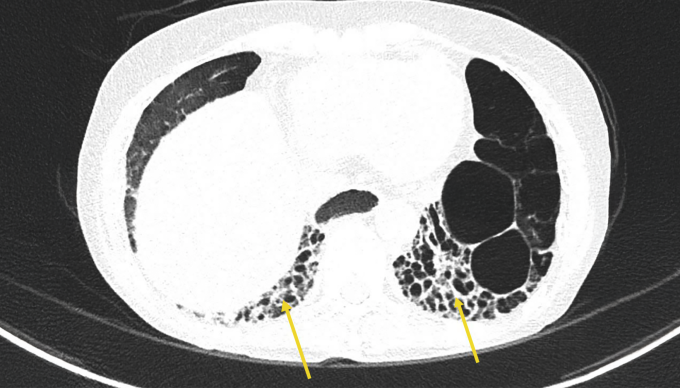

Ảnh CT phổi cho thấy bà Mỹ bị giãn phế quản và tổn thương mô kẽ dạng tổ ong hai đáy phổi và nhiều tổn thương khác. Ảnh: Bệnh viện Đa khoa Tâm Anh